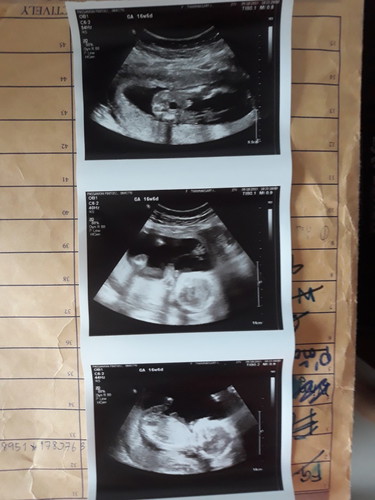

สอบถามเพศหน่อยคะ

อยากทราบเพศ ใครดูออกบ้างคะรูปแรก

ภาพไม่ชัดเลยค่ะ หมอไม่บอกหรอคะว่าอะไร เราเดาว่าน่าจะชายค่ะ ไม่รู้ว่าใช่ไข่ไหม เพราะไม่ชัดค่ะ

ดูภาพบนสุดนะคะ ถ้าตรงระหว่างขาเป็นเรียบๆคือ ผญ. ถ้ามีจุกนูนๆ ออกมา ผช.ค่ะ

น่าจะผู้หญิงนะคะ ถ้าผู้ชายตรงกลางน่าจะโผล่ๆแบบนี้นะคะ 😂😂😂

ผู้หญิงค่ะ ถ้าผู้ชายจะมีแหลมๆแบบนี้ออกมาระหว่างขาน้องค่ะ

น่าจะผู้หญิงค่ะ เพราะถ้าเป็นชายจะมีแบบยื้นออกมา

น่าจะ ผญ ค่า บ้านนี้หมอก็บอกน่าจะสาวน้อยเหมือนกันค่ะ

ผู้หญิงค่ะ ถ้าผู้ชายจะแหลมๆ อันนี้เรียบกริบเลย

ผู้หญิง แน่นอน จร้า ไม่มีไอจู๋โผล่ 5555😆😆😆